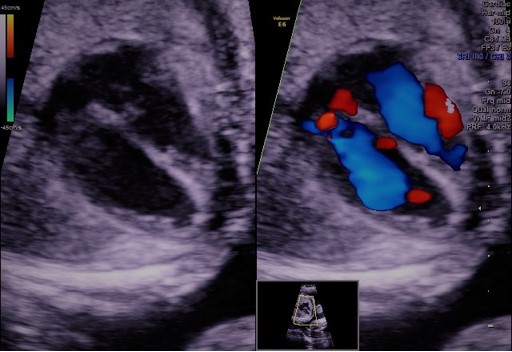

מומי לב מולדים הם מהנפוצים במומים המולדים. יכולים להיות ממצא מבודד או כחלק מתמונה שלמה של ממצאים אשר יכולים להיות חלק מסינדרום.

קיימת חשיבות עליונה באיתור מומים לבביים טרם הלידה על מנת לאפשר טיפול מיטבי כמידת האפשר במקרים בהם ההורים מבקשים לבצע ככול שביכולתם למען היילוד כמו כן לתת להורים לעתיד את כל המידע האפשרי על מנת להתכונן לבאות.

במסגרת ההכשרה של ההתמחות ברפואת העובר אותה ביצע ד"ר דובדבני הוקדש פרק נפרד לסקירת לב העובר בהנחיית קרדיולוגים מהמובילים בלונדון-אנגליה. ד"ר דובדבני סיים בהצלחה הכשרה זו והוסמך לביצוע בדיקת לב העובר.